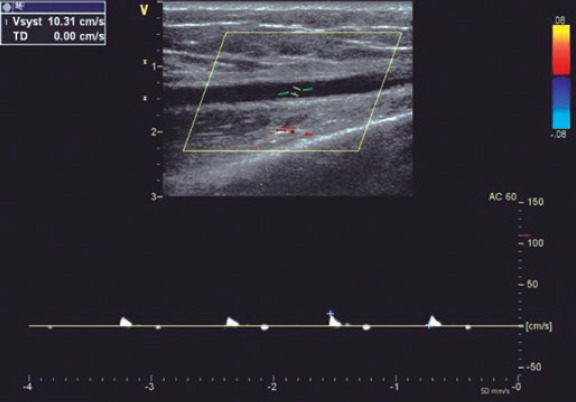

Methods: This prospective study enrolled 427 patients who underwent coronary angiography or angioplasty via transradial access. The forearm arteries were evaluated by ultrasound. If RAO was present, follow-up ultrasound examinations were performed at 1 and 3 months postprocedure.

Results: Our study population included 288 men (67.4%) and 139 women (32.6%). The mean age was 61.9 ± 11.1 years. RAO occurred in 48 patients (11.24%), and spontaneous recanalization was observed within 3 months in 15 patients (32.6%). On multivariate analysis, independent predictors of RAO were younger age (OR, 0.642; 95%CI, 0.480-0.858; P = .031), low periprocedural systolic blood pressure (OR, 0.598; 95%CI, 0.415-0.862; P = .007), a small radial diameter (OR, 0.371; 95%CI, 0.323-0.618; P = .031), insufficient anticoagulation (OR, 0.287; 95%CI, 0.163-0.505; P < .001), occlusive hemostasis (OR, 0.128; 95%CI, 0.047-0.353; P < .001), and long duration of hemostasis. The overall incidence of RA anatomic variations was 14.8% (n = 63). Among these, 40 patients (63.5%) had a high radial origin, 18 (28.6%) had extreme RA tortuosity, and 5 (7.9%) had a complete radioulnar loop.